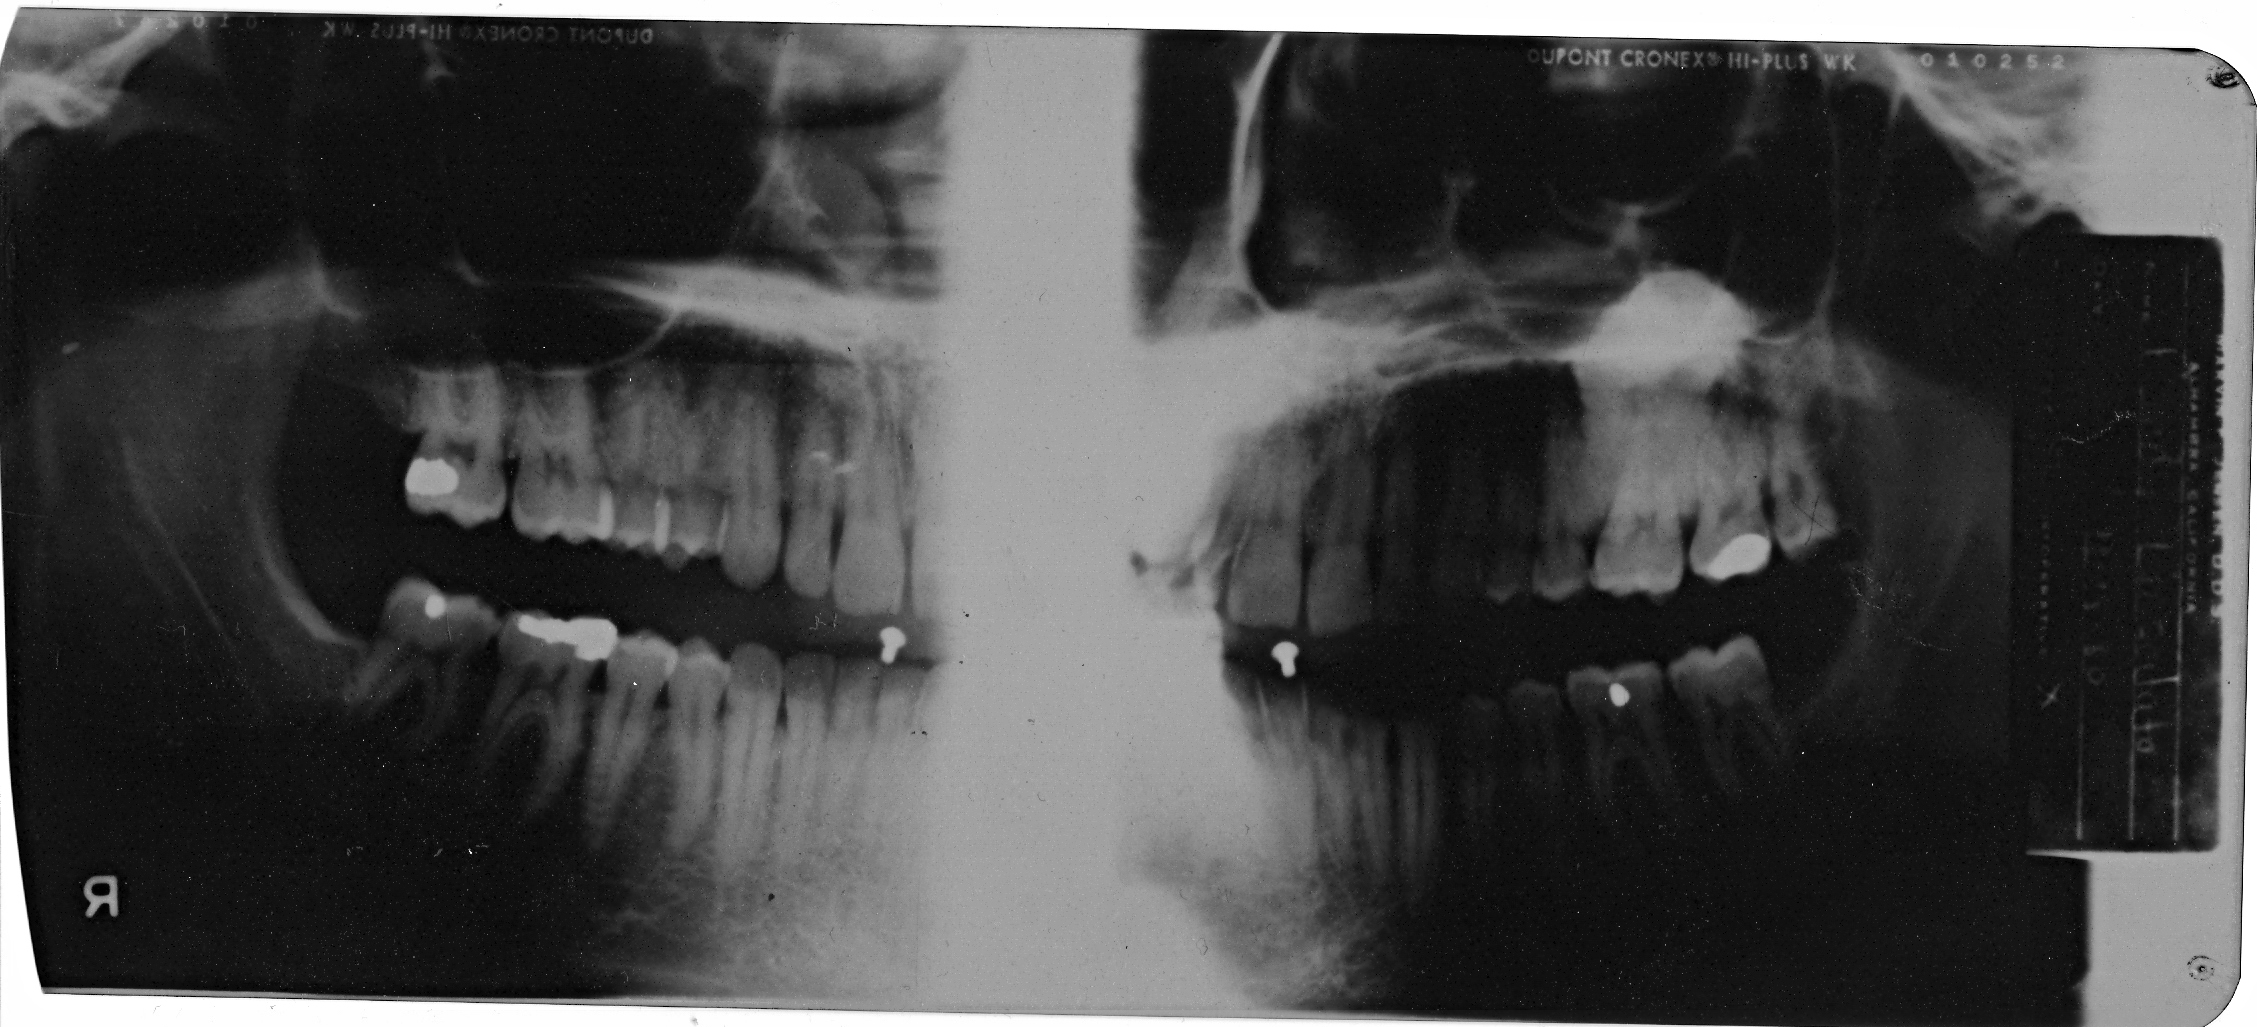

Below are x-rays taken

in 1980 and 1995 which clearly show the bone mass Osteoma involving my

lower sinus and extending down around the roots of teeth 14 and 15

1980 x-ray